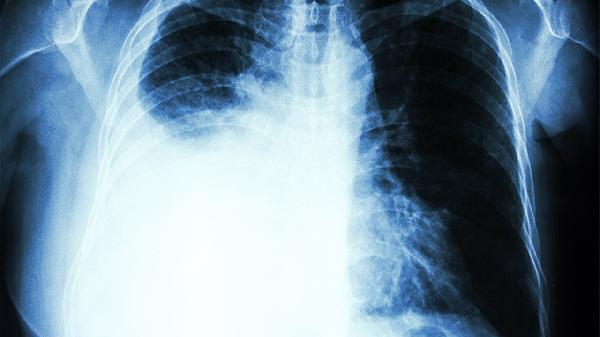

由于疼痛反射性抑制呼吸运动,患者常出现浅快呼吸。严重时可能导致通气不足,出现胸闷气短。多根肋骨骨折可能引起反常呼吸运动,即吸气时胸壁内陷、呼气时外凸。

严重骨折可能损伤胸膜或肺组织,出现咯血、皮下气肿等症状。多发性骨折可能引发连枷胸,导致呼吸困难、血氧下降等危急情况。高龄患者可能出现肺炎等并发症。